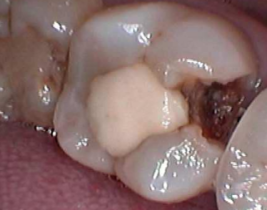

第二阶段(崩解):腐蚀持续进行,牙釉质这个坚硬的外壳终于支撑不住了,从内部开始坍塌。就像被虫子从内部蛀空的木头,表面看只有一个小点,但内部已经空了。当表面的牙釉质薄到一定程度,在一次正常的咀嚼或刷牙受力下,它就会突然破裂,形成一个您能明显感知到的“洞”。